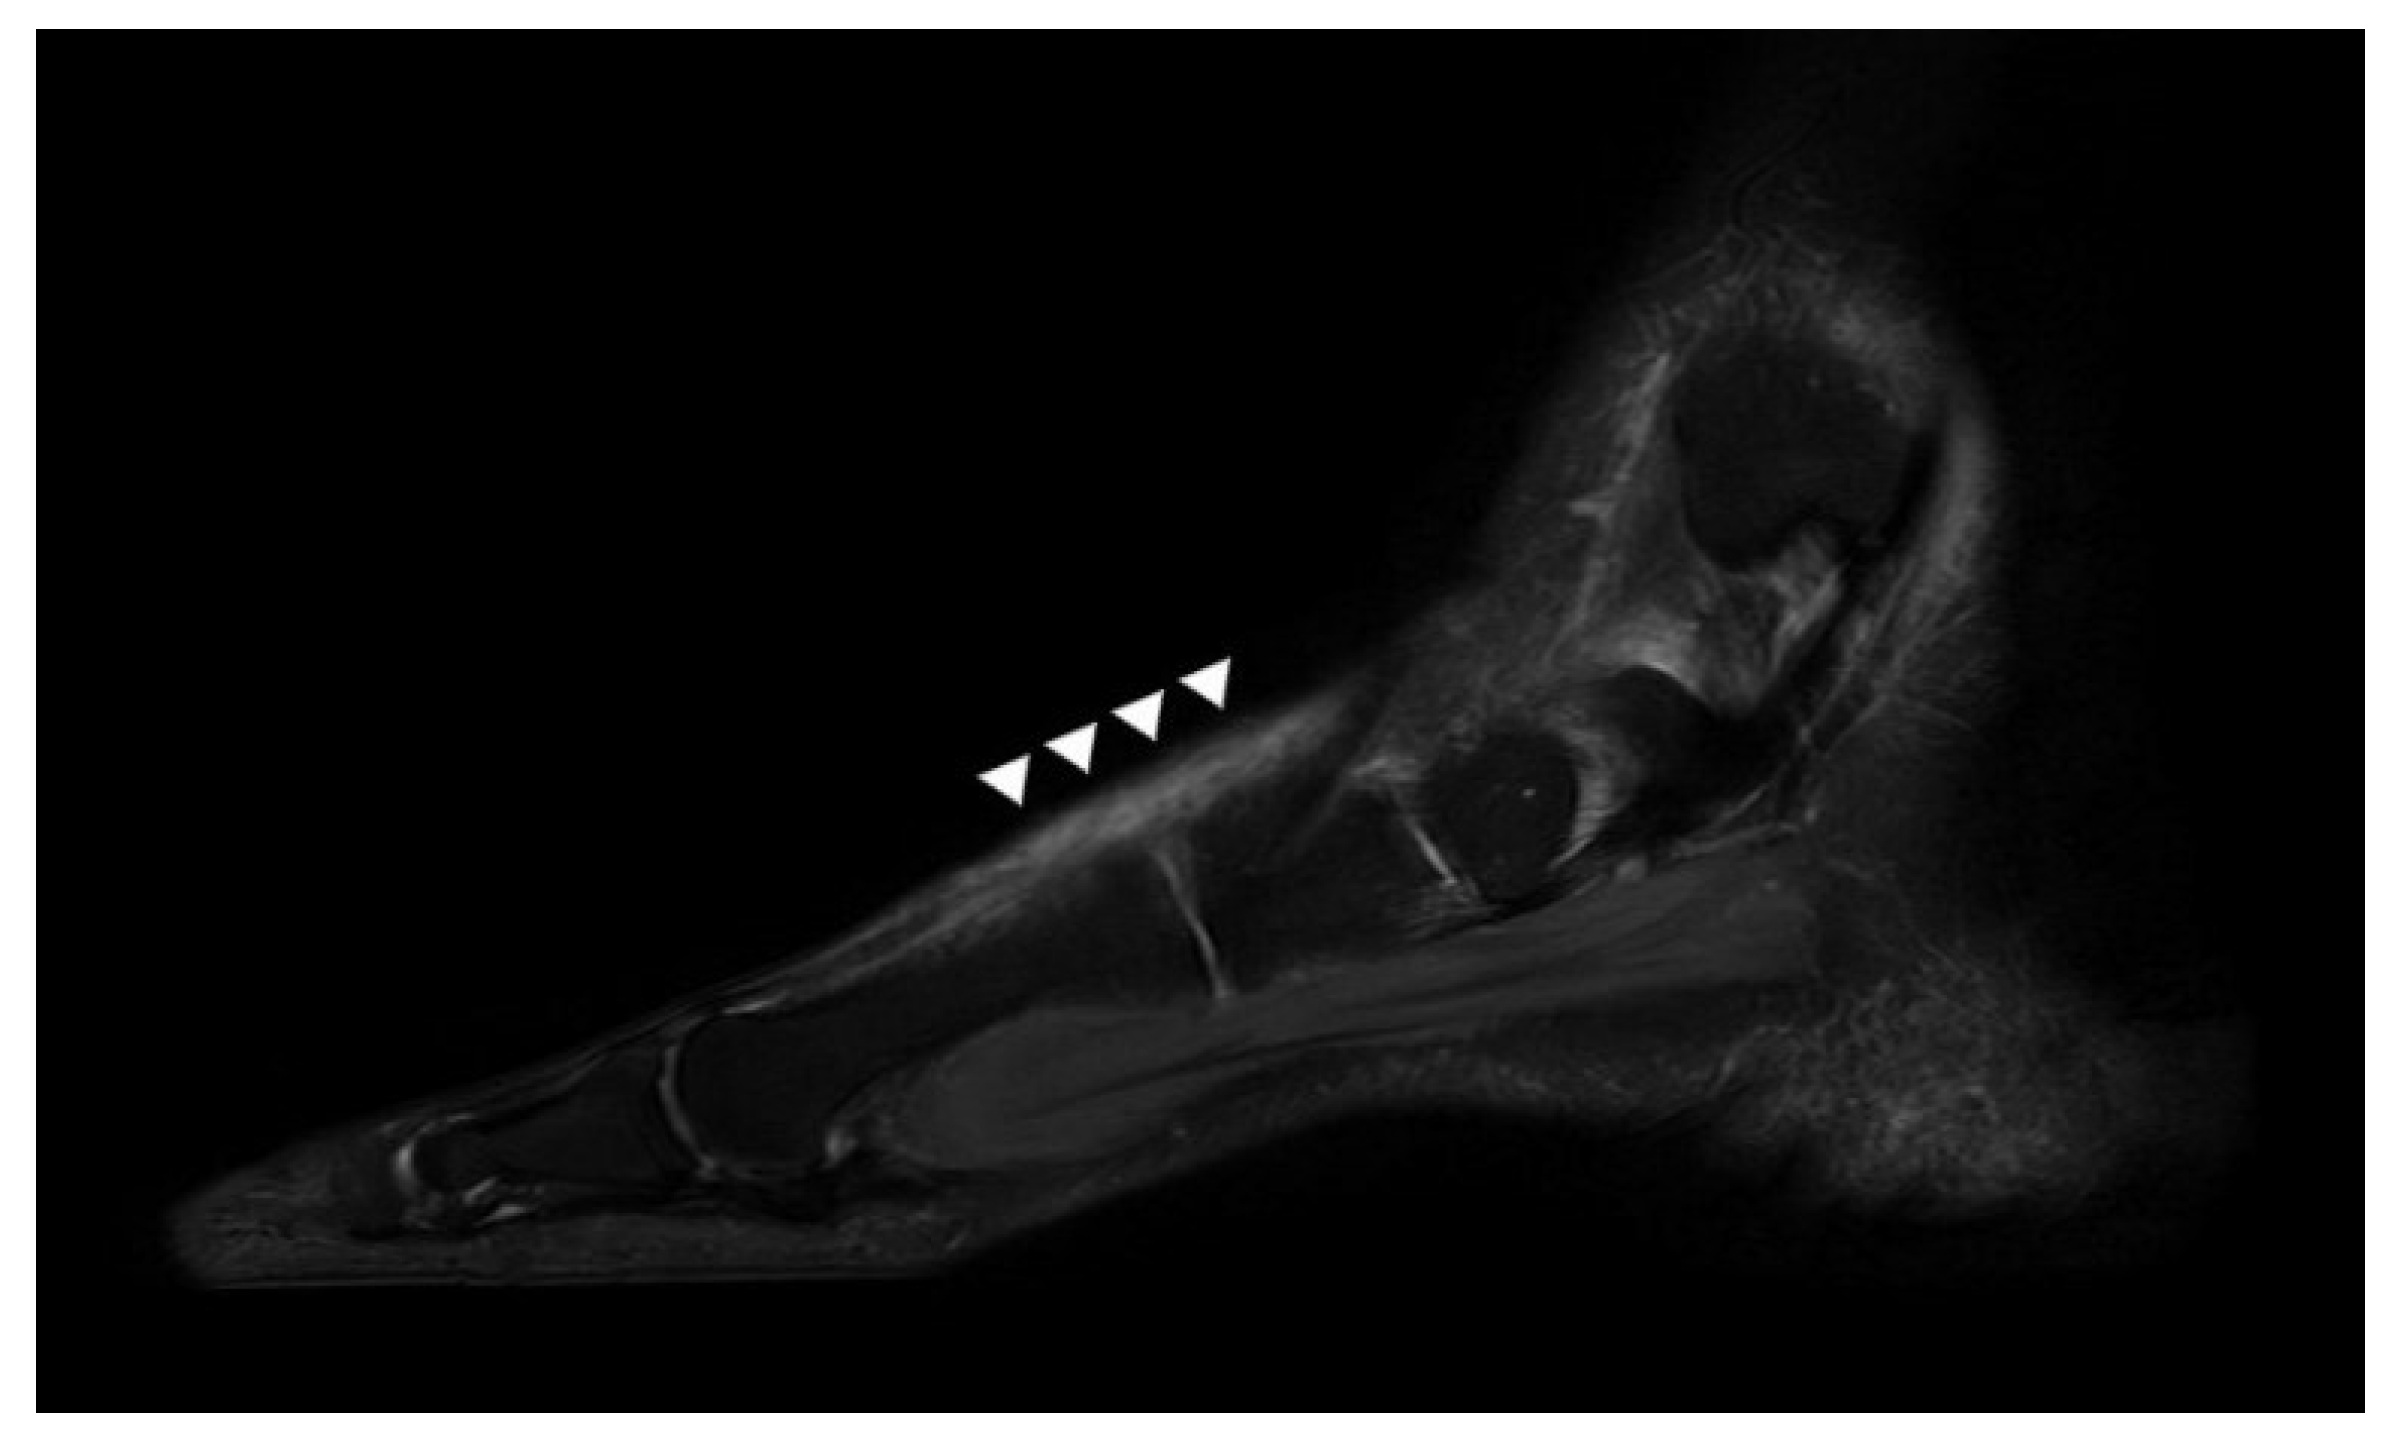

2.1. Preoperative Evaluation